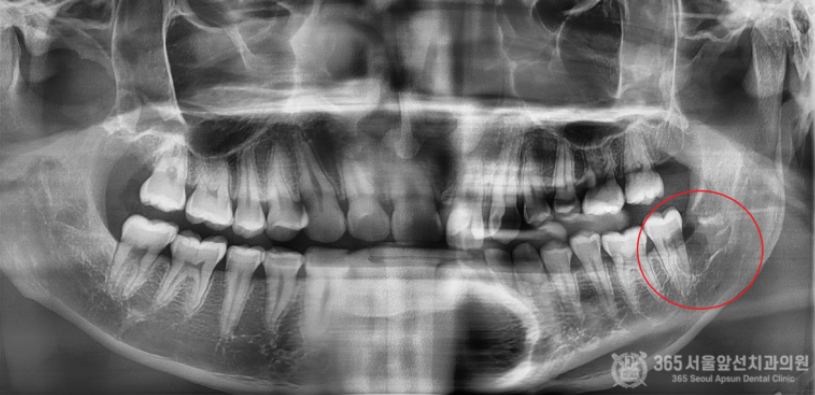

아래턱에 매복사랑니가 있는데, 집근처 동네치과에서 발치가 불가능하다고 대학병원에 가보라고 했어요. 오늘은 완전수평 매복 사랑니의 발치 증례를 소개해드리겠습니다. 집 근처 치과에 방문했다가 완전수평 매복사랑니 발치가 불가능하다는 판정을 받은 환자분께서 내원하셨습니다. 촬영일시 : 2024.05.15. 초진 엑스레이 사진입니다. 완전히 수평으로 매복되어 있으며, 신경관과 뿌리가 겹쳐져 있는 양상이 관찰됩니다. 환자분께선 발치가 불가능할까봐 걱정이 많으셨으나 걱정하지말라고 안심시켜드리고 매복 사랑니 발치를 진행했습니다 ㅎㅎ 촬영일시 : 2024.05.15. 3차원 CT 영상입니다. 뼈 속에 완전히 파묻힌 사랑니를 볼 수 있습니다. 촬영일시 : 2024.05.15. 신경관과 뿌리가 겹쳐져 있는 양상도 관찰됩니다. 조심스럽고 안전한 발치가 필수적이겠습니다. 촬영일시 : 2024.05.15. 발치 후 엑스레이 사진입니다. 발치에 소요된 시간은 총 10분으로 정확하고 빠르게 발치해드렸습니다. 빠르고 정확한 진료를 추구하는 강동우 대표원장이었습니다. 365서울앞선치과의원은 365일 늘 가까운 서울대학교 치과병원을 지향합니다! [ 치료기간: 2024년 5월15일 ] ※ 365서울앞선치과의원의 모든 포스팅은 각 진료과 의료진이 직접 작성합니다. 365서울앞선치과의원 블로그의 임상 케이스 게시물은 환자분께 의학적으로 정확하고 상세한 정보를 드리기 위해 각 진료과 의료진이 직접 작성하며, 모든 증례 사진은 본원 의료진이 직접 시술한 증례를 촬영한 것으로, 의료법 제23조, 제56조에 의거하며 환자분의 동의를 얻어 포스팅에 사용하였습니다. 또한 해당 케이스는 본 환자분의 치료 결과이며, 환자 상태에 따라 치료의 결과는 달라질 수 있습니다. |